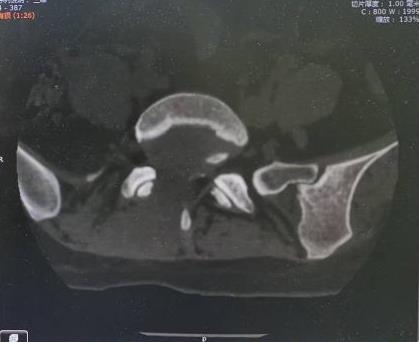

• 单侧双通道内镜下椎间盘切除术治疗钙化型腰椎间盘突出症的临床疗效分析

2025, 31(8):26-31. DOI: 10.12235/E20240693

摘要 (204) HTML (119) PDF 3.09 M (137) 评论 (0) 收藏

摘要:目的 观察单侧双通道内镜(UBE)下椎间盘切除术治疗钙化型腰椎间盘突出症(CLDH)的临床疗效。方法 回顾性分析2020年1月-2022年1月在该院行UBE下腰椎间盘切除术的25例单节段CLDH患者的临床资料。记录手术时间、术后住院时间和术后并发症情况。采用腰腿痛视觉模拟评分法(VAS)评分、腰椎日本骨科协会(JOA)评分和Oswestry功能障碍指数(ODI),评估术前、术后3 d、术后1个月和末次随访的临床疗效。末次随访时,采用改良Macnab标准,评估优良率。结果 术后随访12~24个月,平均(15.60±2.60)个月。手术时间为(58.67±10.73)min,术后住院时间为(4.65±0.63)d。术后3 d、术后1个月和末次随访时的VAS评分和ODI明显低于术前,JOA评分明显高于术前,差异均有统计学意义(P < 0.05)。末次随访时,根据改良的Macnab标准,15例为优,9例为良,1例为可,优良率为96.00%(24/25)。术后并发症:1例神经根腹侧硬膜囊撕裂,长度约5 mm,未行硬膜囊修补术,术后嘱患者卧床5 d,给予补液治疗,患者下床活动未诉头痛等不适,术后MRI显示:未见硬膜外大量积液;1例出现下肢感觉障碍,给予营养神经药物对症治疗,术后1个月随访时恢复。术后影像学检查显示:游离钙化组织基本被完全切除,神经根得到充分减压。末次随访时,未发现复发病例。结论 UBE下腰椎间盘切除术治疗CLDH安全、有效,值得应用于临床。